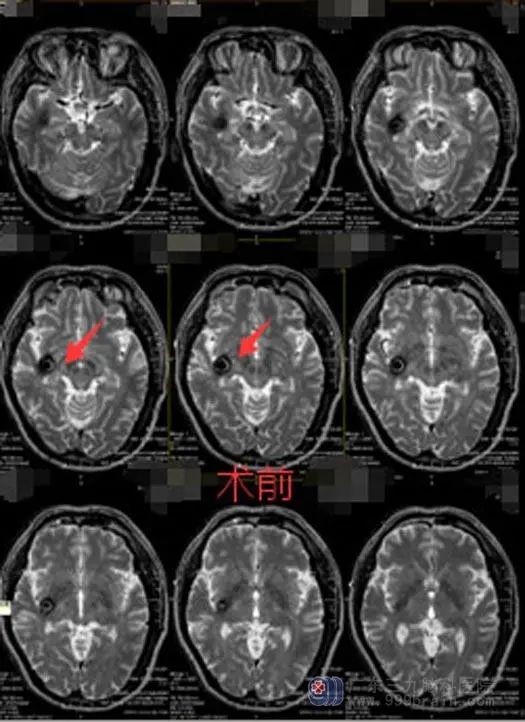

邓先生说,他的父亲经常觉得头晕、头痛,断断续续的有一年时间。本以为会慢慢地缓解,没想到症状是越来越严重,近期发病的时候还会伴有呕吐。他带着父亲在当地医院治疗,但是头痛、头晕症状没有好转。

头部MRI检查,提示:左侧颞叶占位性病变,考虑海绵状血管瘤伴出血可能。

邓先生的父亲具有手术指征,主治医生团队顺利切除了血管瘤,术中无明显副损伤。手术后,邓先生父亲的头痛、头晕症状已经有了明显的好转。